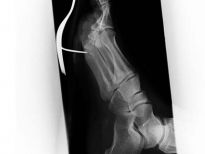

Bu röntgenler gerçek!